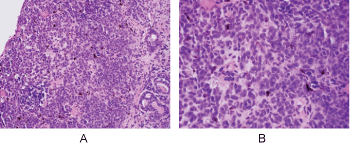

Histologic evaluation disclosed a pigmented focally ulcerated mass surrounded by a zone of pigmentation within both the mucosa and some of the seromucinous glands. The mass was composed of atypical oval to polygonal cells with scant to modest amounts of cytoplasm containing scattered brown pigment. Morphologically, the neoplasm was consistent with malignant melanoma (Figure 2A and Figure 2B). No in-situ component of the melanoma was seen. The mucosa over the mass was ulcerated and the neoplastic cells invaded the underlying soft tissues and surrounded and destroyed the entrapped seromucinous glands. At the periphery of the mass, the seromucinous glands contained pigment morphologically identical to that seen in the melanoma (Figure 3A). The pigment lay in the cuboidal to low column cells lining the lumen of the glands (Figure 3B). Immunohistochemical staining for S-100 protein, HMB-45 and melan A showed the glandular cells to be immunoreactive for these three antigens (Figure 4A, Figure 4B and Figure 4C). The cuboidal cells also contained granular pigment positive by the Fontana-Masson reaction. This black pigment was most intense near the laminal surface of the cells (Figure 5). Occasional Fontana-Masson positive cells were present in the overlying mucosa near the melanoma and occasionally loose in the stroma (Figure 6).

Figure 3: A) Seromucinous glands of nasal mucosa containing melanin pigment (H+E, X200); B) Prominent melanosis of epithelium of glands (H+E, X600). View Figure 3